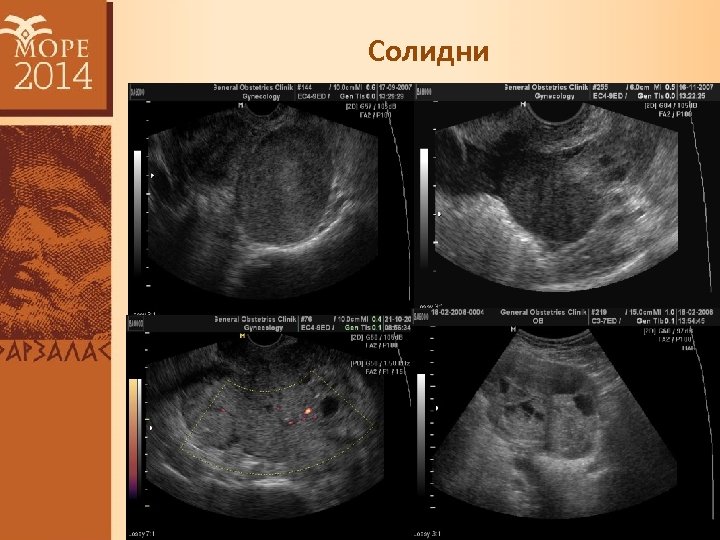

Солидни

Риск от малигненост 1. Еднокамерни кисти - 0, 6% 2. Еднокамерни-солидни (unilocular solid cysts) – 33% 3. Многокамерни (multilocular) – 10% 4. Многокамерни-солидни (multilocular solid) – 41% 5. Солидни – 62%